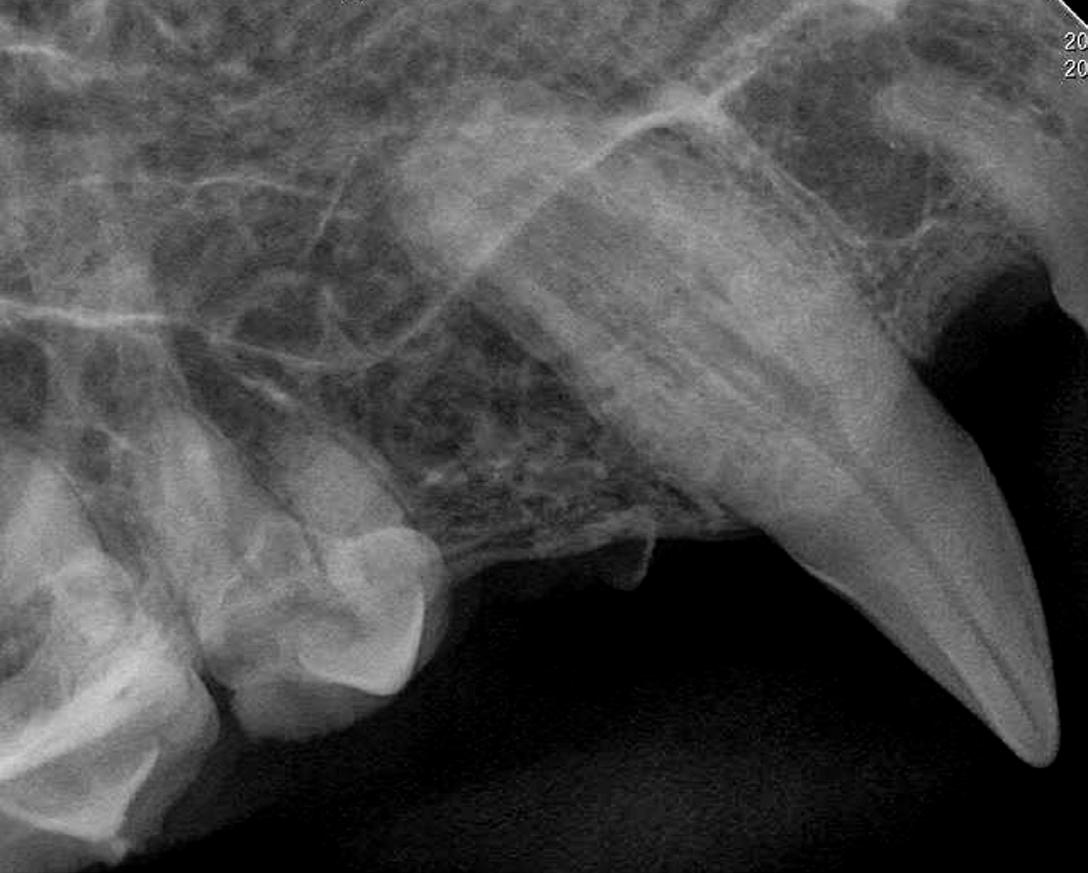

Discomfort and pain associated with dental and oral disease is often difficult to assess in veterinary patients. A conscious oral exam presents a diagnostic challenge, as dogs and cats rarely show obvious signs of dental illness. Intraoral radiographs provide the clinician with important information to obtain a diagnosis and begin planning for treatment of oral pathology not visible during direct examination.

Interpretation of dental radiographs is like the evaluation of full-body radiographs. Start by scanning the complete image for quality, positioning, and overall impression. Note any abnormalities, including anatomical structures that are not present or appear abnormal. This includes fractures, missing teeth, and areas of osseous lucency. Next, evaluate each tooth beginning with the crown and continuing with the root, periodontal ligament space, pulp chamber/root canals, and surrounding bone (cancellous and cortical).

PERIODONTAL DISEASES

Identifying the alveolar margin (alveolar crest), the cementoenamel junction (CEJ), and the lamina dura is important in the radiographic evaluation of periodontal disease. The lamina dura is a radiographically visible, thin radiopaque line that represents a layer of compact bone lining the alveolus. It appears dense and uniform in the younger animal, becoming ill-defined in the aged patient or in various disease states. The lamina dura is separated from the root by a radiolucent line, which represents the periodontal ligament space.

Periodontal disease can be classified from stages 1 to 4 based on the severity of radiographic and clinical findings. The toothsupporting bone height in periodontal disease decreases as inflammation and infection increases and bone is resorbed. Around 40% of the bone’s thickness must be destroyed before it is detected radiographically. Distribution of bone loss is classified as either localized or generalized, depending on the number of areas affected. Specific areas of bone loss may be classified as horizontal (perpendicular to the tooth) or vertical (angular along the side of the root).